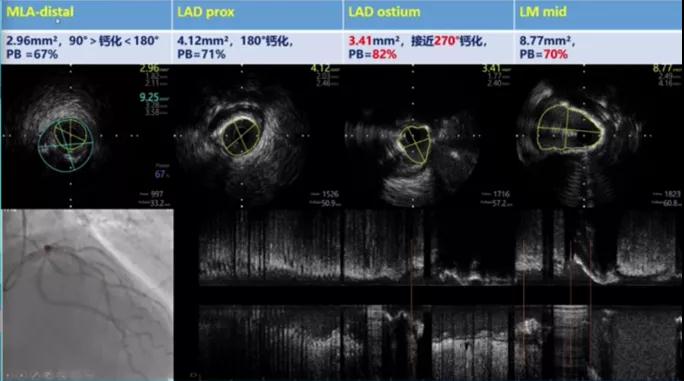

该病例SYNTAX评分中危,结合患者自身意愿在IABP辅助下行PCI治疗,术前行IVUS评估病变,术中使用比伐芦定抗凝降低出血风险。进行IVUS成像后可以发现,LAD-LM偏心性钙化病变,LM狭窄最严重处钙化环角度270°,LCX以纤维钙化斑块为主,接近开口处存在90-180°钙化环。

【内科观点】作为冠脉钙化领域经验丰富的专家,叶飞教授谈到:根据IVUS我们仅仅可以知道LM末端存在270°的钙化环,但是无法明确钙化的深度,如果可以使用OCT,应该可以进一步明确钙化深度从而更好地选择预处理策略。而就本病例而言,可以尝试使用高压球囊预扩张。

【内科观点】钱菊英教授则表示,仔细分析IVUS的影像可以发现钙化环9点钟方向存在缺口,因此推测这一钙化病变并不是很厚,强有力的预扩张应该可以将钙化环打开。而预扩张的效果直接关系到患者的远期预后。

术后复查IVUS可见LM末端钙化环被打开,支架膨胀、贴壁效果良好。